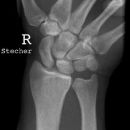

Handgelenk seitlich

Beurteilungskriterien

• Neigung der distalen Radiusgelenkfläche in der Sagittalebene: 10 – 15°

• Kontinuierliche Verlängerungsachse durch Radius, Lunatum, Capitatum und Os metacarpale III. Kontinuität von Handrücken und Unterarmrückfläche (Luxation, nicht-exakte Einstellung? -> Proc.styloideus ulnae im hinteren Radiusdrittel?)

• Scapholunärer Winkel 30 – 60°

• Verstreichen und Ventralverlagerung der volaren Fettstreifen vor dem M.flexor digitorum profundus und M.pronator quadratus

• Grundsätzlich gilt: unklare Verhältnisse -> CT-Indikation